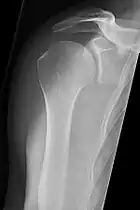

The standard projection protocols in the UK are:[15]

- Humerus - AP and Lateral

- Elbow - AP and Lateral. Radial head projections available on request

Lateral projection

Anteroposterior projection